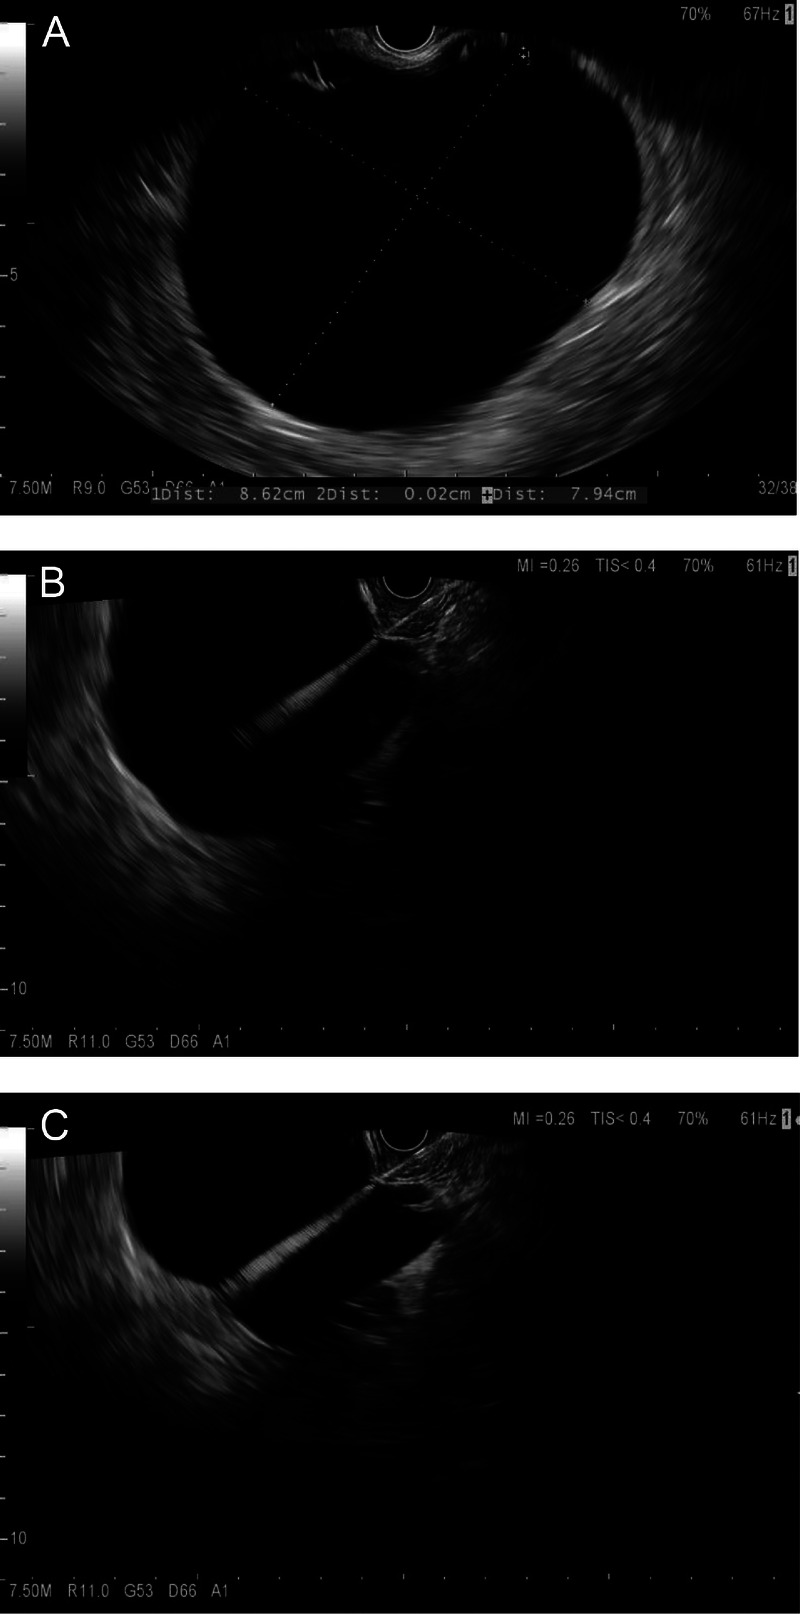

Background and objectives: An accurate diagnosis is crucial for the clinical management of pancreatic cystic neoplasm (PCN). EUS-guided through-the-needle biopsy (EUS-TTNB) is a novel technique for improving the accuracy of PCN diagnosis. There is insufficient evidence about the efficacy of EUS-TTNB. This study aims to evaluate the feasibility and diagnostic performance of EUS-TTNB for PCN.

Methods: Between June 2015 and July 2023, we prospectively enrolled 454 patients with a clinical concern for PCN in our database. After excluding those diagnosed with pancreatic cancer, pseudocysts, or other no-neoplasms, we assessed 326 patients with 329 cysts undergoing EUS-guided fine-needle-aspiration (EUS-FNA) or EUS-TTNB for evaluation. The primary indicators were tissue acquisition yield and diagnostic yield. The cyst characteristics (size, location, the presence of septation, mural nodule, and solid mass) and the number of biopsy samples were chosen for the analysis of factors associated with diagnostic performance.

Results: There were 220 (67.5%) females and 106 (32.5%) males, and the median patient age was 50 years (range, 18-88). There were 329 cysts sampled by FNA and 143 by TTNB. The median cyst size was 31.5 mm (range, 6.9-114.0). The diagnostic yields of FNA and TTNB were 35.7% (112/314) and 57.5% (73/127), respectively (P < 0.001). Special cyst types were diagnosed by TTNB in 58 (45.7%, 58/127) cysts, 19 of which had surgical pathology. Fifteen of 19 TTNB diagnoses were concordant with the surgical pathology.

Conclusion: EUS-TTNB is an option to improve the diagnosis of PCN. Standardized procedures and appropriate indications for TTNB need to be studied.